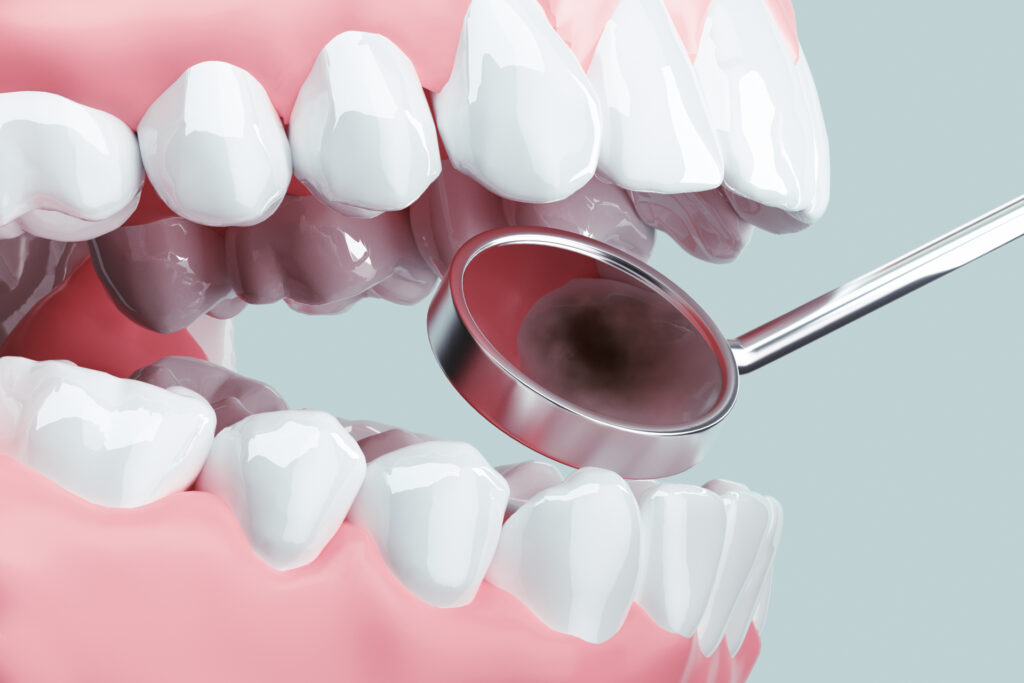

「一般歯科」とは虫歯治療、歯周病治療など、歯の病気全般の治療のことです。

虫歯や歯周病の治療が必要のないように予防することと、早期発見・治療が大切です。

痛みがないまま進行して、症状に気付いたときにはかなり進行しているのがむし歯や歯周病の特徴です。